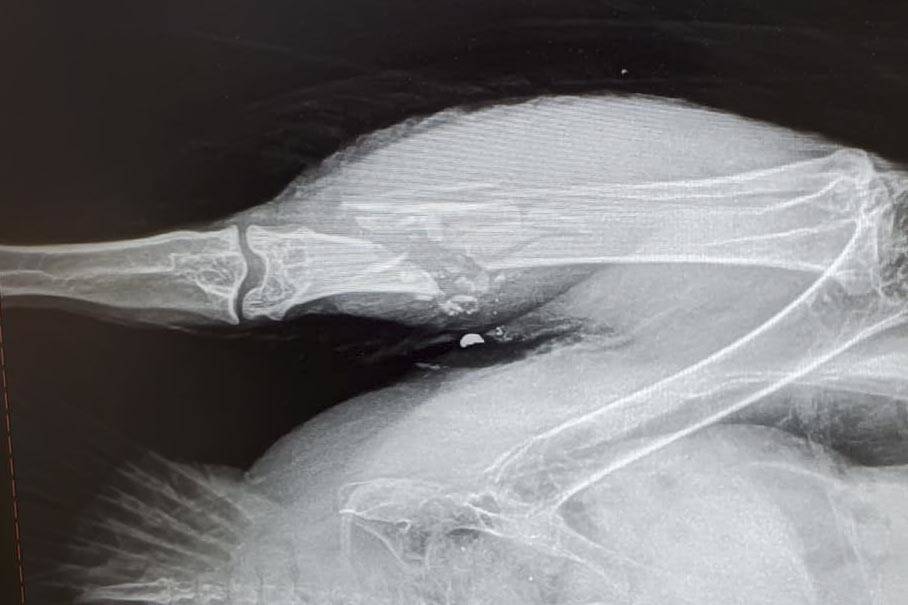

For the eagle rescued near Montana Creek Road on Dec. 22, its rescuers weren’t even aware it was such a case until the Alaska Raptor Center in Sitka X-rayed the bird, and passed word that it had been shot, Benner said. The bird, whose pelvis was shattered and had mounting lead poisoning from the lead shot (shotgun ammunition) that is illegal in Alaska, had to be euthanized, Benner said.

“Apparently she was shot in the beak and the rest of the right wing. I think it was a bullet as opposed to shot, but she had been out in the wild for two weeks after she had been shot,” Benner said. “She was shot in the wing, so she couldn’t fly. The impact of the bullet also caused a detached retina in her left eye.”